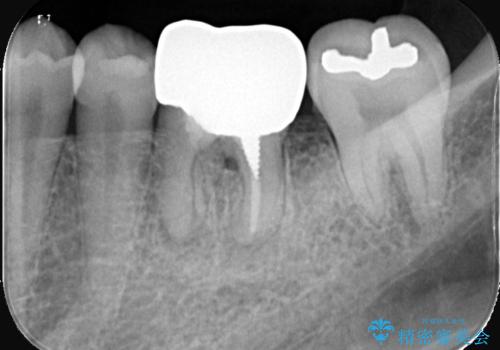

インプラント治療は手術が一度で完了し、術後の痛みもほとんどありませんでした。

機能面・審美面ともに大きく改善され、患者様にも大変ご満足いただけました。